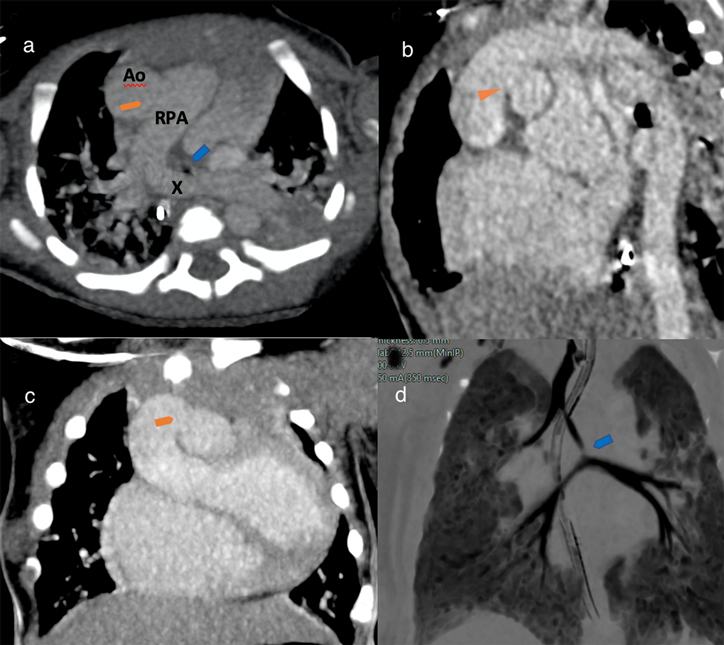

A full-term baby (male, birth weight 3.1 kg) was admitted with signs and symptoms of heart failure, but without cyanosis, at 10 days of life. His pulse oximeter indicated 96% on room air with respiratory rate 56/min, heart rate 147/min, blood pressure 69/35 mmHg. Chest X-ray showed plethoric lung fields and cardiomegaly (Fig. 1). Oxygen was given 1 L/min via a nasal cannula. Frusemide and spironolactone are started. His hemoglobin was 20.0 g/dL, hematocrit 58%, total white blood cells 13,600 µ/L, platelets 181,000 µ/L, CRP 0.1 mg/L, with normal renal function (urea 4.6 mmol/L, Na 133 mmol/L, K 4.5 mmol/L, Cl 95 mmol/L, Ca 2.35 mmol/L). An urgent 2D-Echo showed a large VSD, AP window (Fig. 2) and also PA sling suspected. Thoracic CT angiography confirmed Type 2a PA sling with severe tracheal stenosis. The so-called “tracheal bronchus” gave rise to the right upper lobe; its branching being as if at the usually expected location for the carina. The bifurcation to the right lower lobe and the left lung in this patient was present lower down with abnormal orientation (the bronchi more horizontally oriented than usual). The left PA is located at the T6–7 level just above the carina which resulted in distal airway stenosis (Fig. 3). The SVCs were bilateral structures. Lung volumes appeared fair bilaterally. The coronary arterial origins were normal. Cardiac MRI illustrated the right atrium and the right ventricle dilated, and also reconfirmed PA sling of the left PA as well as AP window between the distal AscAo and the right main PA (Supplementary Movie S1).

Fig. 1 Chest X-ray (at 10 days old) shows cardiomegaly. Nasogastric tube in situ.